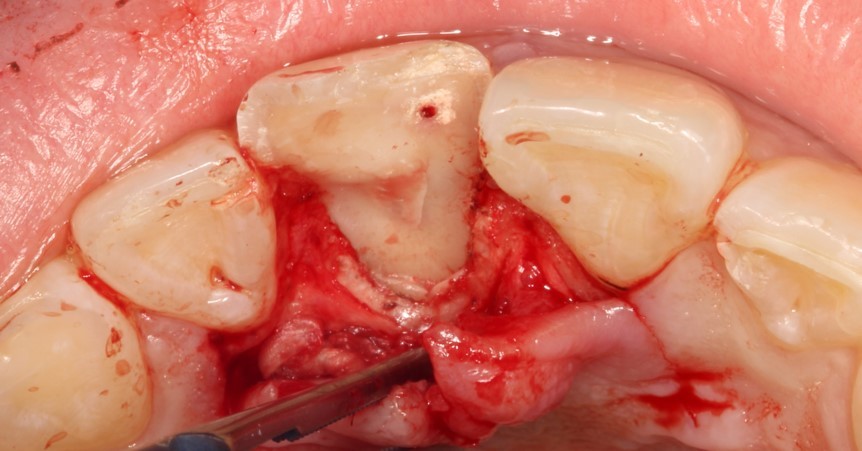

На данной фотографии продемонстрирована припасовка осколка зуба. Далее зуб и осколок был вычищен и адгезивно подготовлен к фиксации.

После фиксации отломка были убраны излишки жидкотекучего композита